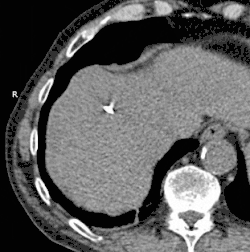

In der Krebsbehandlung können Tumoren durch Vereisung zerstört werden, besonders in Fällen wenn eine chirurgische Entfernung nicht möglich ist. Anwendung findet diese Technik bei Krebs in Knochen, Brust, Gebärmutterhals, Auge, Niere, Leber, Lunge und in der Prostata.[1] (Siehe hierzu auch den Abschnitt „Kryochirurgie“ im Artikel „Kryotherapie“.) Zur Optimierung der Wirkung wird der Prozess von Kühlen und Auftauen meist einige Male wiederholt.